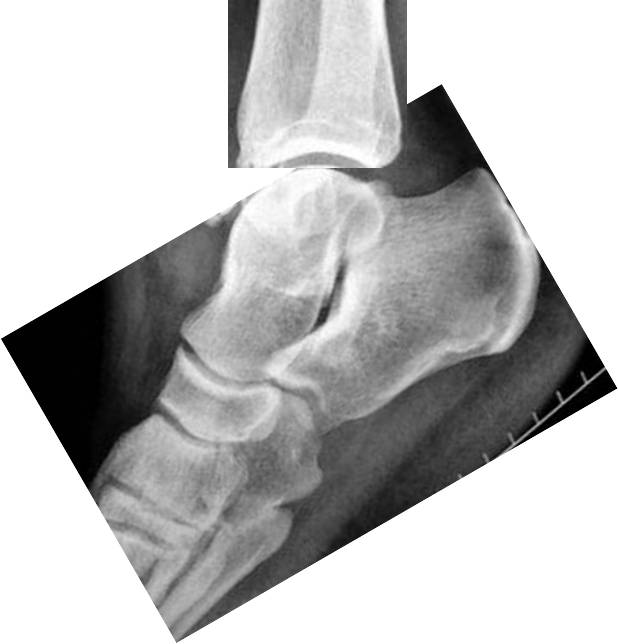

Дефект глубокий, обширный, в молодом возрасте лучше оперировать. Иногда в выборе доступа помогает КТ в положении максимального подошвенного сгибания стопы: если дефект таранной кости при этом выходит из-под большеберцовой, лучше идти простым и менее травматичным передним доступом. На монтаже из представленной Вами рентгенограммы стопа согнута на 30°, дефект практически "вышел". Поскольку он расположен не по центру, то с большой степенью вероятности обнажится при гораздо меньшем угле.